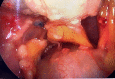

Fig. 1

Nodular Excresences in the Posterior cul-de-sac.